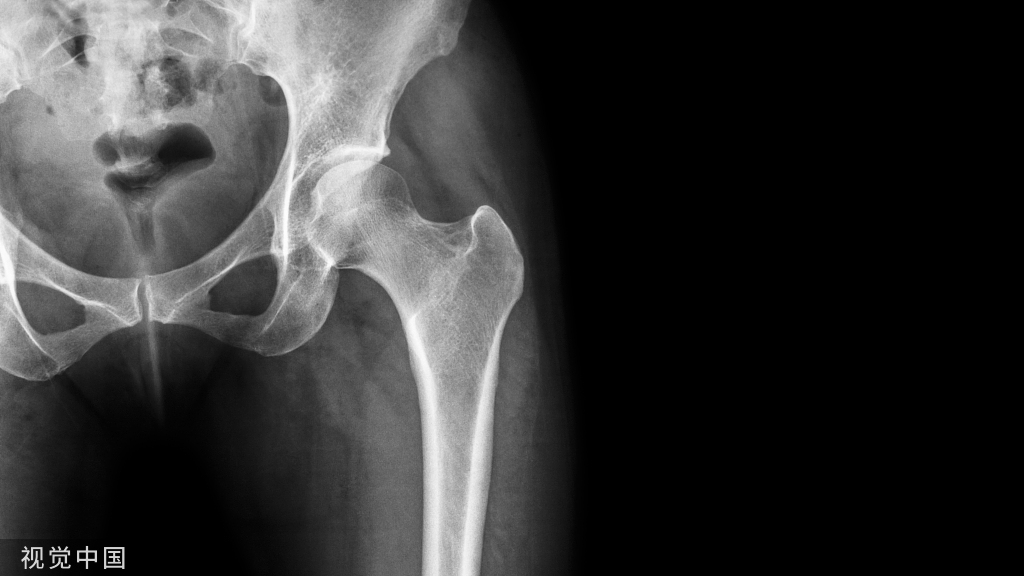

股骨转子间、转子下骨折骨折是一种多发于老年人的骨折,虽然常见,但并不简单。医生的手术技巧对治疗预后非常重要!

完善的术前影像学检查和熟练的阅片技巧

单纯的骨盆平片是不够的,需拍患肢全长片以排除远端的骨折